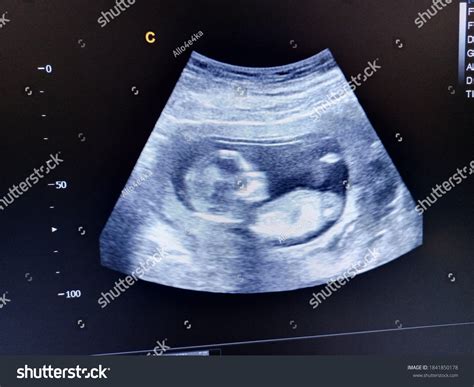

At 15 weeks, the fetus undergoes significant development. Some of the key milestones include:

• Size and Appearance: The baby is about the size of an apple, measuring approximately 4 inches (10.1 cm) in length and weighing around 2.5 ounces (70 grams).

• Sensory Development: The baby’s senses are becoming more acute. Eyelids remain fused shut, but the eyes can perceive changes in light. The baby can also hear sounds from the outside world.

• Organ Development: The baby’s organs are developing rapidly. The liver produces red blood cells, and the pancreas is forming. The baby’s heart beats strongly, and the lungs are starting to form.

• Movement: The baby becomes more active, with increased kicking, punching, and rolling movements. Although these movements are not yet felt by the mother, they can be seen during the ultrasound.